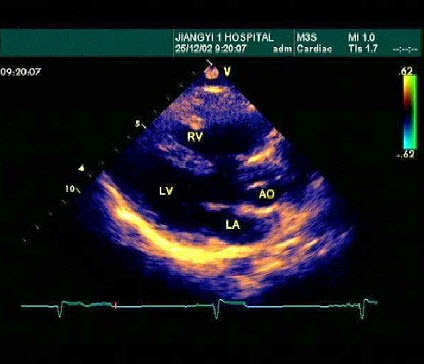

某患者左室长轴切面超声心动图如图所示,诊断为()

A.正常声像图

B.主动脉瓣关闭不全

C.二尖瓣关闭不全

D.室间隔缺损

E.房间隔缺损